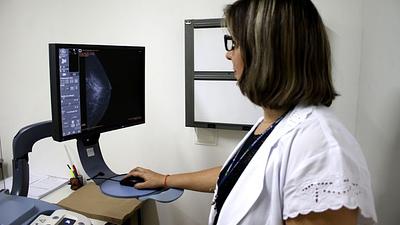

Escassez de mamógrafos dificulta prevenção do câncer de mama

O Brasil tem uma cobertura muito baixa de mamografias: 24%. O ideal recomendado pela Organização Mundial da Saúde é de 70%.